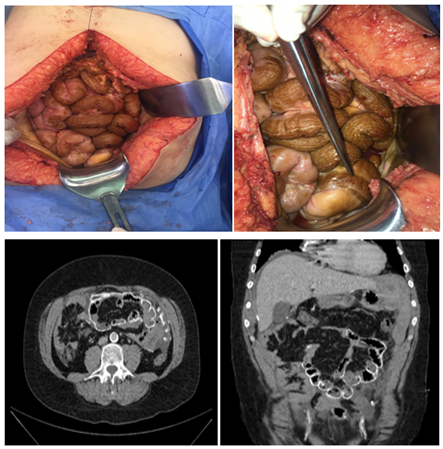

We present the case of a 37-year-old male patient with a history of arterial hypertension and end-stage renal disease in PD the thirteen previous years. At the ED he presented with bleeding through the peritoneal dialysis catheter after valsalva maneuvers due to sudden vomiting. Initial assessment revealed hypotension, tachycardia and pallor, without mental status alterations and a referred abdominal pain in the mesogastrium and epigastrium without peritoneal irritation. Initial blood workup showed mild leukocytosis and neutrophilia, anemia, high azotees, no electrolyte imbalance and a normal abdominal ultrasound Figure 1. Subsequent follow up anemization and abdominal CT findings compatible with perihepatic, perisplenic and pelvic fluid associated with hyperdense peripheral enhancement of bowels and mesentery/peritoneum urged surgical intervention. Laparotomy findings were a massive hemoperitoneum with no initial clear bleeding site, parietal/visceral peritoneum, small/large bowel and mesentery with chronic inflammatory changes, thickening and dark-brown coloration. After a thorough exploration a gastroepiploic artery branch in the gastric curvature presented persistent oozing with appropriate management. No intestinal obstruction was evident. Postoperative evolution was favourable, with renal replacement therapy by hemodialysis initiated without setbacks. A post-operative RBC transfusion was necessary with subsequent stabilization of hemoglobin, modulation of inflammatory response, decrease in leukocytosis, neutrophilia and CRP. Blood cultures, peritoneal fluid cultures and a negative adenosine deaminase in peritoneal fluid. Two weeks follow up was performed with no early surgical complications.

Figure 1 CT Scan images.